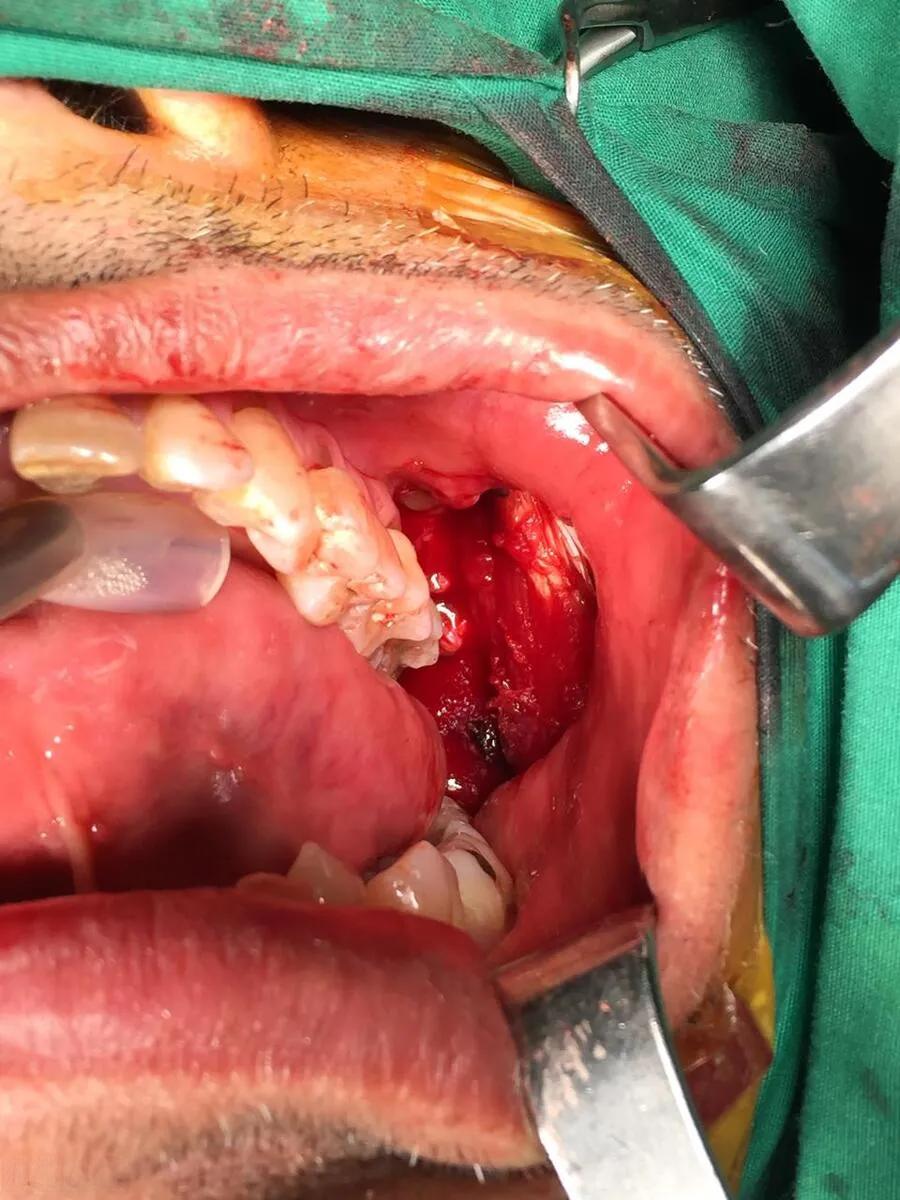

嚼槟榔会增加口腔癌风险,这已经是一个不争的事实。根据中南大学湘雅医院的调查,在口腔颌面外科50位住院患者中,有45人患口腔癌,其中44人有长期、大量咀嚼槟榔病史。这个惊人的数据揭示了槟榔与口腔癌之间的密切关联。

槟榔之所以能致癌,主要是因为它含有多种活性成分和代谢产物,如槟榔生物碱、槟榔鞣质、槟榔特异性亚硝胺和活性氧等。这些物质具有细胞毒性、遗传毒性甚至直接致癌性。长期咀嚼槟榔会导致口腔黏膜下纤维化,这是一种癌前病变,有2.3%—7.6%的可能性转变为口腔癌。